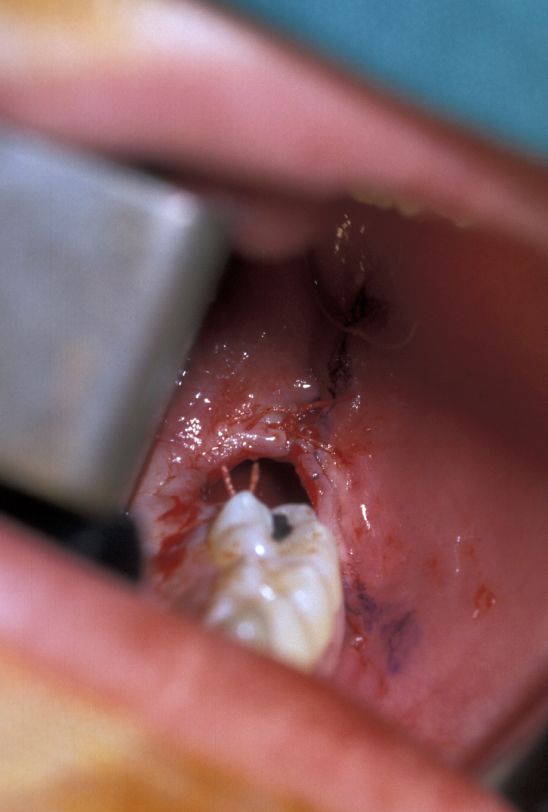

Surgery involves the same access as for the removal of the tooth, except that great care must be taken not to damage the cementum of the root surface as this can lead to ankylosis of the tooth and subsequent failure of eruption. An adequate amount of the crown should be exposed to allow attachment of the bracket and chain. Prior to bonding the bracket to the tooth, the area should be as uncontaminated as possible. Bleeding should be arrested as much as practicable with the use of local application of vasoconstrictors (as is added to some local anaesthetics) or the use of diathermy. Once the area is prepared, the tooth surface should be washed with saline or water and then prepared for bonding either with acid etch or with self-etch priming agents. The latter offer the advantage that they do not need to be rinsed off, need less time to prepare the tooth and are to some extent hydrophilic.

Once the tooth surface has been prepared the bracket can be secured either with chemical- or light-cured composite. The bracket should be tested to ensure that it is securely in place prior to wound closure. The chain or ligature can either exit through the wound margin on the alveolar ridge or through a stab incision elsewhere if it is felt that this would give a better vector of traction to align the tooth. With teeth that are significantly ectopic or are close to the roots of adjacent teeth, it is sometimes useful for the orthodontist to be present at the time of surgery. This allows an assessment of the relationship of the canine to adjacent structures and to plan the vector of traction that will be most appropriate.